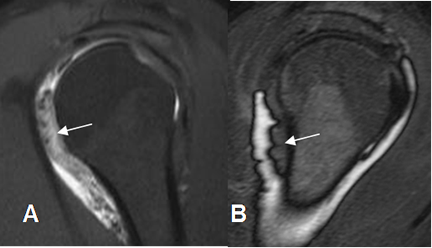

Fig 147. Capsulitis adhesiva.

A y B: ArtroRM sagital en STIR. Engrosamiento de la sinovial mayor de 4 mm, por capsulitis adhesiva.

El principal criterio para hacer el diagnóstico, es el engrosamiento de la sinovial mayor de 4 mm, en las secuencias sagitales de RM. (27).

Otros hallazgos en la artroRM son poco o ausencia de llenado del receso axilar o del tendón de la cabeza larga del biceps, irregularidad en la inserción capsular, volumen articular menor de 10 cc y dolor después de la inyección de menos de 10 cc de contraste.(27).